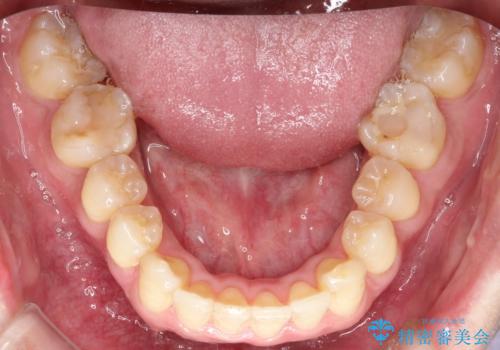

ワイヤーによる全体的ながたつきの矯正治療

- 30代男性

- メタル

- 1年3ヶ月

- 全体的ながたつきを治したいとのことで来院されました。

ワイヤー矯正とマウスピース矯正の二つの器具での治療をご案内し、ワイヤー矯正を選択されました。

インビザラインを装着するのがめんどうなので、ワイヤーの方があっているとのことで今回の治療方法を選択されました。